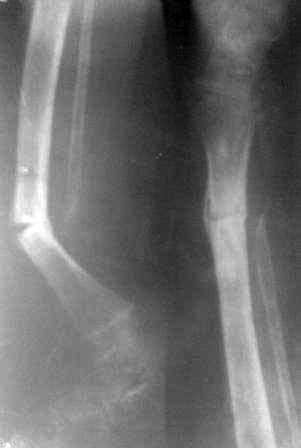

Девочка 2005г.р. В середине 2008 г падает с велосипеда с дедом, возможно был перелом н/з костей левой голени, лечение у знахаря-табиба, но ребенок не смог бегать, часто падал, начал хромать. Май 2009г. обратились к нам, установлен д-з « вялоконсолидирующаяся перелом н/з б/берцовой кости, несросшийся перелом м/берцовой кости со смещением по ширине». Мы решили гипсовая повязка и ходьба с нагрузкой, но по категорическому требованию родителей исправить деформацию м/берцовой кости, произвели операцию ( на свою голову )»о/ репозиция и и/м фиксация спицами м/берцовой кости». Теперь началась самая интересная история! Ч-з недели две в обл. п/о раны м/берцовой открылась свищ с кровянистым выделением, гноя не было, на р-грамме лизис концов отломков м/берцовой кости, к-рый начал прогрессировать, консультирована онкологами, цитология, с подозрением направлена в центральные институты, сделана КТ, онкологическое исключили, в августе попали в остеомиелитический центр, где произведена резекция м/б на протяжение 6-7см, все зажило и выписали (снимок-1). 2010г в мае повторно получила травму, наложена гипсовая повязка (снимок-2) и через 1-2 месяца в одном из центральном институте произведена КДО аппаратом Илизарова , который снят ч-з три месяца (снимок-3) и долго ходила на костылях-мать заставила, как начала наступать, появилась деформация, заказали ортез и так ходила, но деформация прогрессировала, Обратилась к нам в апреле 2012г,(снимок-4) произведена постепенная коррекция на аппарате, и замена на БИОС 01.03.12г плечевым гвоздем, ЭОП нет, поэтому осталась несколько антекурвация (снимок-5), ребенок ч-з неделю начала ходить.Повторный осмотр 22.06.12г- деформация усиливается, за три месяца сращение очень слабое.(снимок-6). (Жаль что многие р-снимки не сохранились, мать обещала хотя бы часть найти)!Что теперь делать?